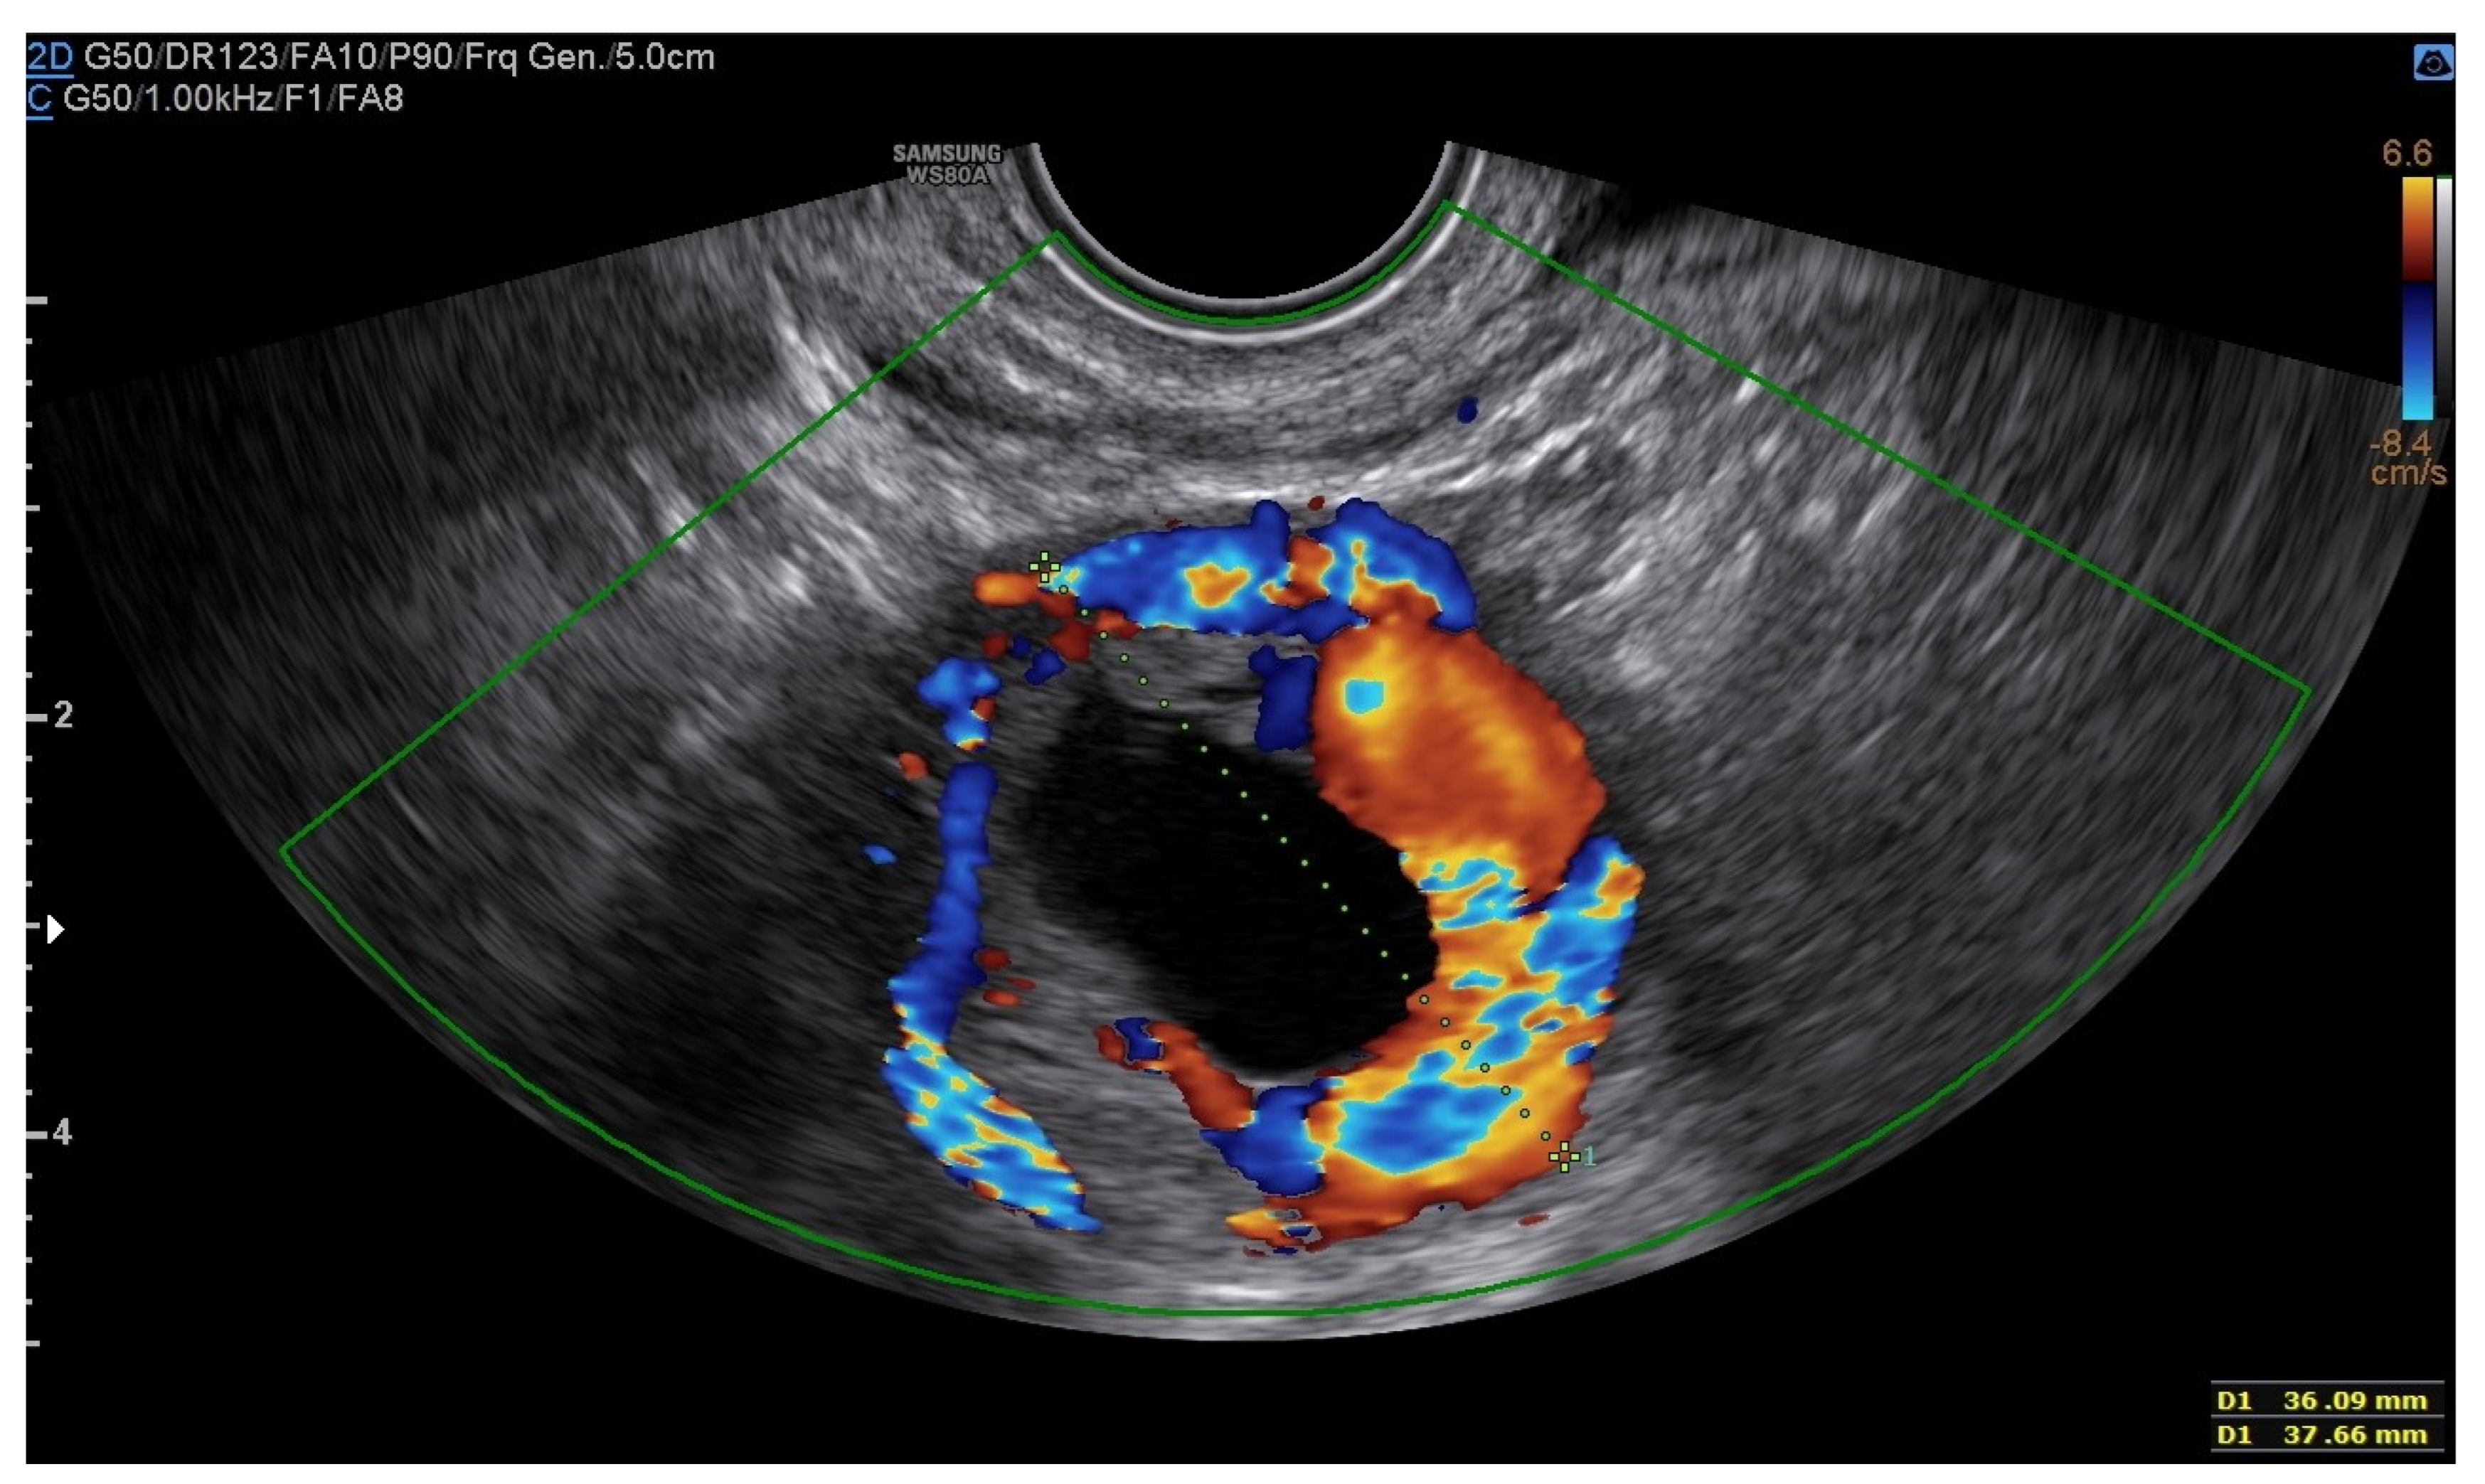

A 25-year-old woman, with a history of left tubal laparoscopic salpingectomy for an ectopic pregnancy, sought medical attention at the hospital’s emergency department after an episode of vaginal bleeding at 5 + 6 weeks of amenorrhea. At Day-1, her β-hCG was 2528 mUI/mL but a transvaginal ultrasound scan (TVUS) showed no clear evidence of pregnancy. Therefore, the patient was admitted with a diagnosis of pregnancy of unknown location (PUL). Upon admission, the patient was clinically and hemodynamically stable and did not report any pain or active bleeding. Serial measurement of her β-hCG in the following days was consistent with a suboptimal growth (3696 at Day-2, 5898 at Day-4, 10,984 at Day-7). Repeated TVUSs failed to show sure evidence of pregnancy until Day-7, when an intramural vascularized mass of 27 × 8 × 20 mm, with a gestational sac of 7 mm, a yolk sac and a 2 mm embryo with a heartbeat, was detected (Figure 1). Pelvic nuclear magnetic resonance (NMR) performed at Day-7 confirmed the presence of an intramyometrial T2-hypointense signal alteration of 20 mm in the right cornual area, surrounded by ectasic vessels, suggestive of interstitial pregnancy (Figure 2). After thorough counselling, a conservative management was proposed and accepted by the patient. The patient was administered a single oral dose of mifepristone 600 mg in combination with multidose systemic MTX 72 mg on days 0, 2, 4 and 6 from diagnosis. Follow-up by TVUS and β-hCG measurement was carried out. By Day-15, β-hCG reached a plateau and started reducing. A TVUS confirmed the termination of the pregnancy by involution of the gestational sac and the presence of the embryo with the disappearance of the fetal heartbeat. After 22 days from treatment, while the pregnancy was disappearing, in the same site, TVUS showed the appearance of a myometrial tubular hypoechoic region of 37 × 38 mm with an intensely vascular and multidirectional flow. Spectral Doppler ultrasound showed a low-resistance, high-velocity (peak systolic velocity of 128 cm/s) flow pattern, suggestive of uterine arteriovenous malformation (AVM) in the location of the previous interstitial pregnancy (Figure 3). The patient remained asymptomatic. To avoid menstrual bleeding and minimize the risk of metrorrhagia, a depot 3.75 mg shot of a GnRH analogue was administered every 28 days for 4 months. Considering the desire to preserve the fertility of the patient, the absence of guidelines for the treatment of AVM and the good results presented in the literature on uterine artery embolization as a conservative treatment, we performed a right uterine artery embolization, with sonographic resolution of the AVM within 3 months (Figure 4). We accessed the right common femoral artery and a 5-Fr introducing an angiographic sheath was placed. A 5-Fr Cobra catheter (Cook, Bloomington, IN, USA) was used to perform nonselective angiograms of the internal iliac arteries in order to achieve a general understanding of the vascular anatomy; the right internal iliac artery was selected after creating a Waltman loop with the Cobra catheter. The right uterine artery was selected using a microcatheter ranging from 2.0 to 2.4 Fr. As embolic materials, polyvinyl alcohol particles were used (Contour; Boston Scientific, Cork, Ireland). The rescue treatment had no complications. We present an unpublished case of interstitial pregnancy in a hemodynamically stable woman at an early gestational age successfully treated with medical therapy using MTX and mifepristone, who developed a peculiar complication.

Figure 3. Arteriovenous malformation (AVM).